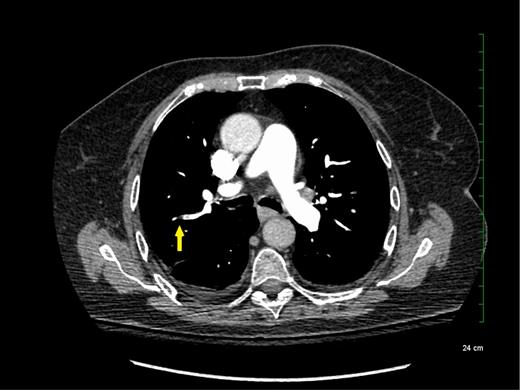

Subsegmental pulmonary embolism on computed tomographic pulmonary angiography.

Although SSPE diagnoses are increasing with advancements in technology, the true incidence of SSPE remains unclear. It is unknown whether these filling defects reported by radiologists are actual thrombus or artifacts. Interobserver agreement between radiologists was shown to be low for the diagnosis of SSPE in the emergency room (κ = 0.38; 95% confidence intervals [95% CIs], 0.0 to 0.89).8,9 Previous studies reported that up to 59% of SSPE diagnoses made clinically were actually false positives upon reinterpretation by a thoracic or more experienced radiologist.10,11 Another study including reinterpretations by 5 radiologists showed that for SSPE diagnosis, at least 1 radiologist disagreed with the initial interpretation in 60% of the cases.12 Given this variability in the certainty of SSPE diagnosis, it is important for clinicians to review the CTPA results and confirm the diagnosis with a thoracic or experienced radiologist to avoid exposing patients to anticoagulant therapy for an artifactual finding.